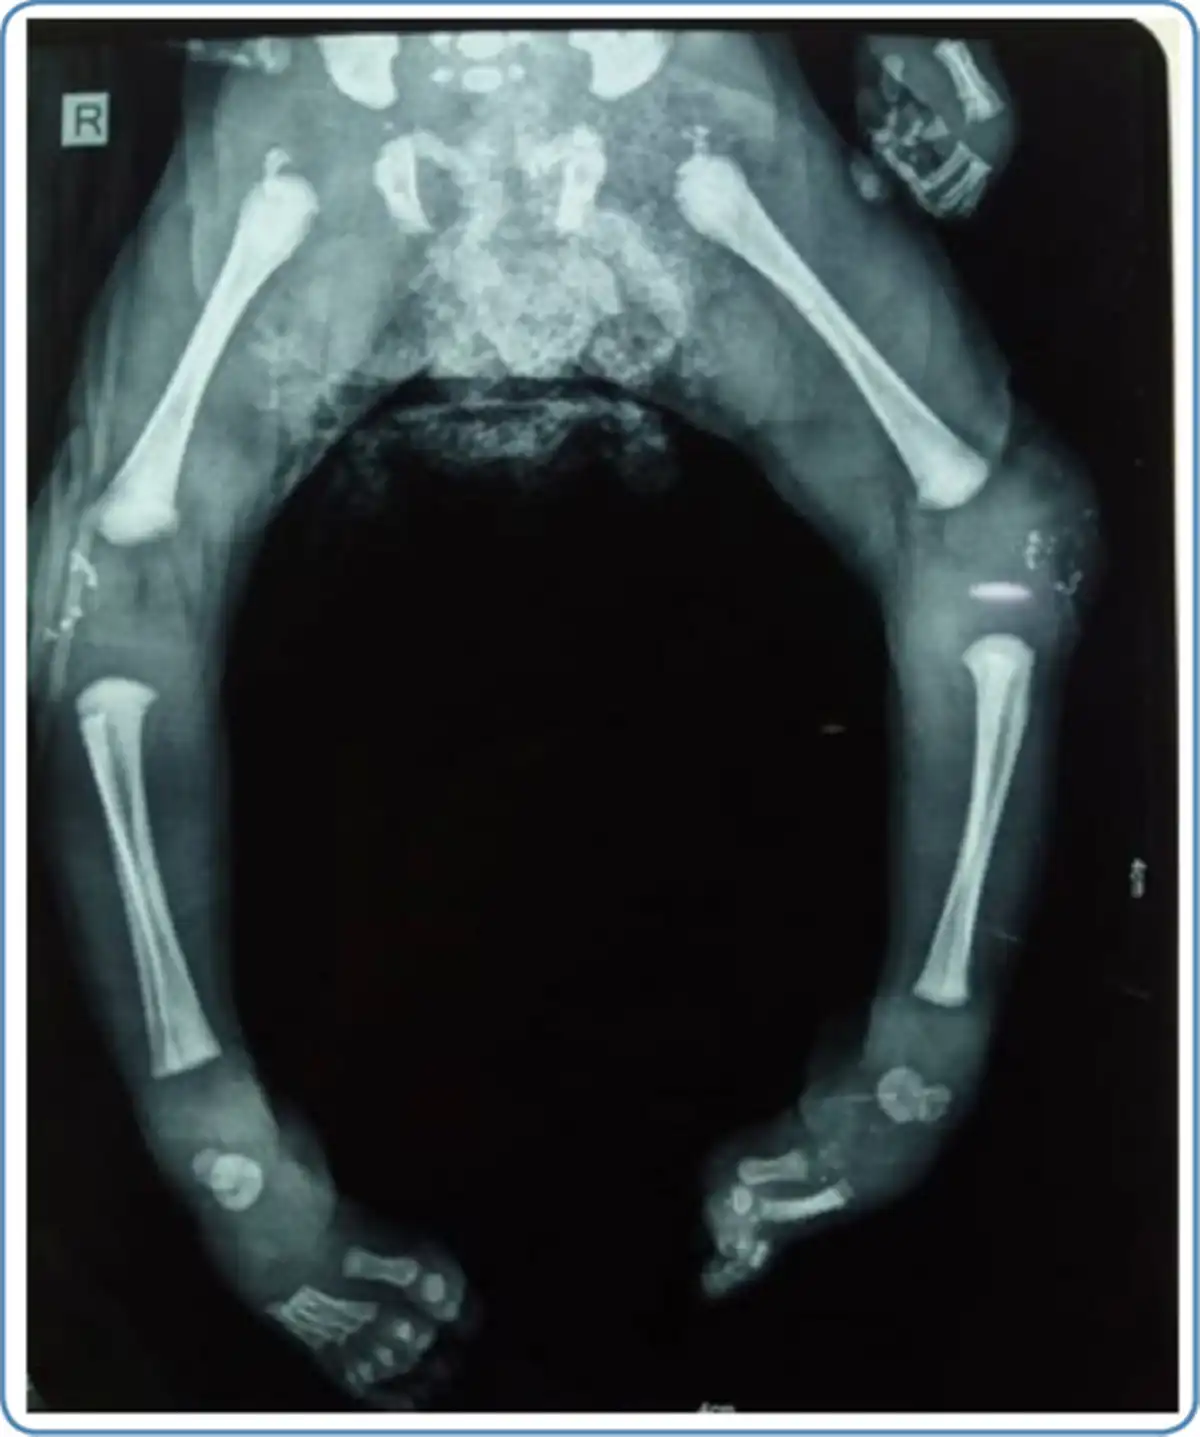

Skeletal abnormalities

Chondrodysplasia punctata at the knee and/ or ankle joints and along the vertebrae in early childhood and rhizomelic shortening are noted in skeletal radiographs in cases with RCDP and Zellweger syndrome (Figure 6). In addition, vertebral cleftsare seen on the skeletal survey in RCDP.

Figure 6

Skeletal radiograph showing chondrodysplasia punctata at the knee joint in a child with rhizomelic chondrodysplasia punctata